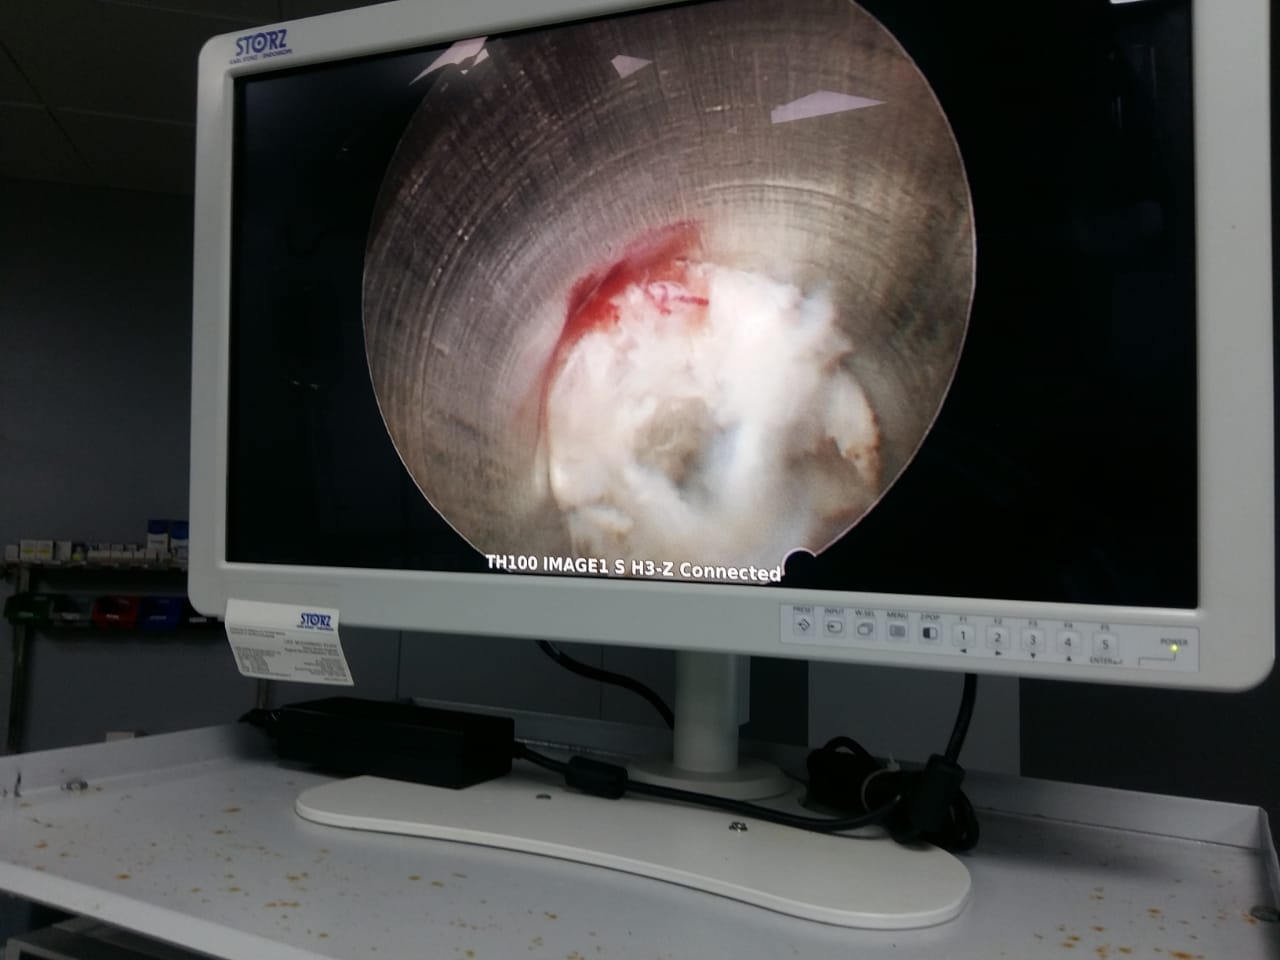

Endoscopic discectomy under Local Anaesthesia.

Removed disc fragment in awake n aware anaesthesia.

Patient was watching the whole procedure at screen and was responding to commands.

Skin incision was just 6 mili meter

No stitch required at end of procedure

Biggest advantage of this procedure is that since patient is awake he will not allow surgeon to injure any neural structure

Endoscopic view of spinal canal

Endoscopic surgery in progress